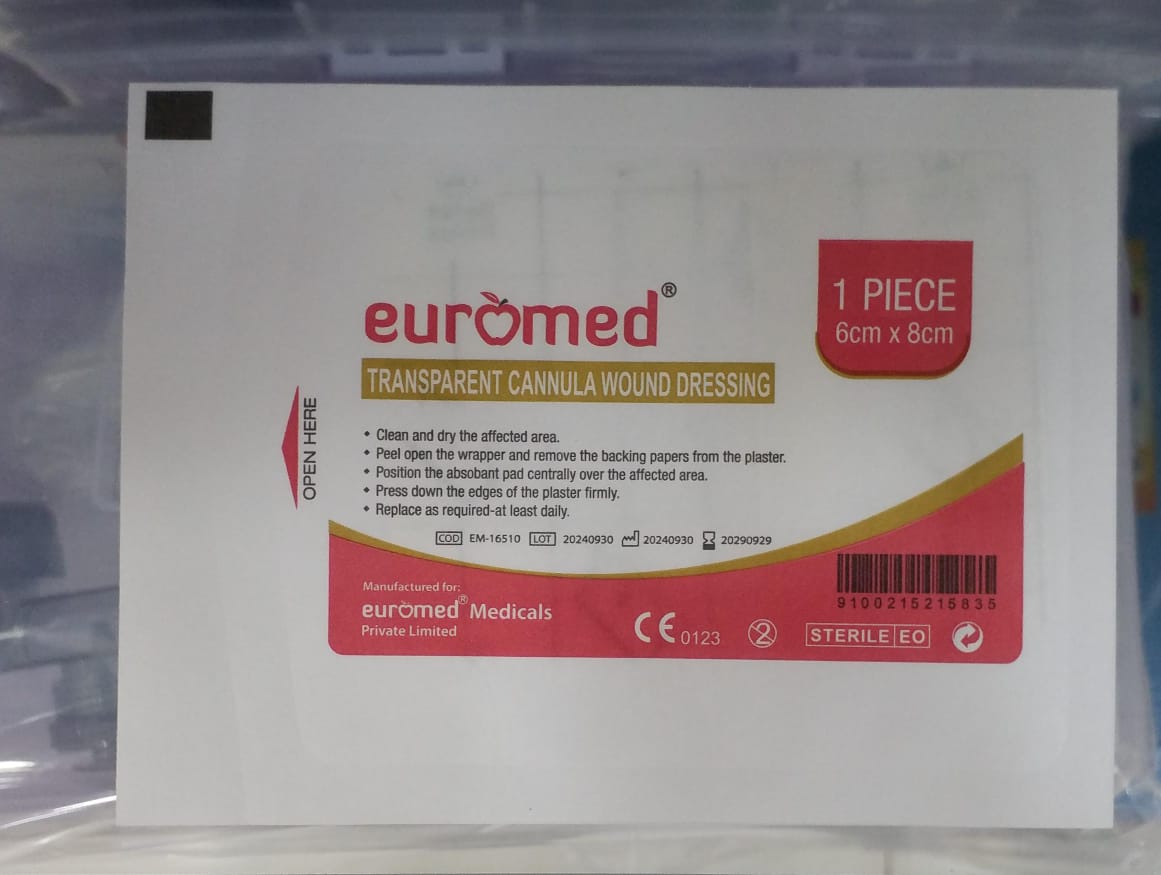

IV CANNNULA FIXING DRESSING

IV CANNNULA FIXING DRESSING